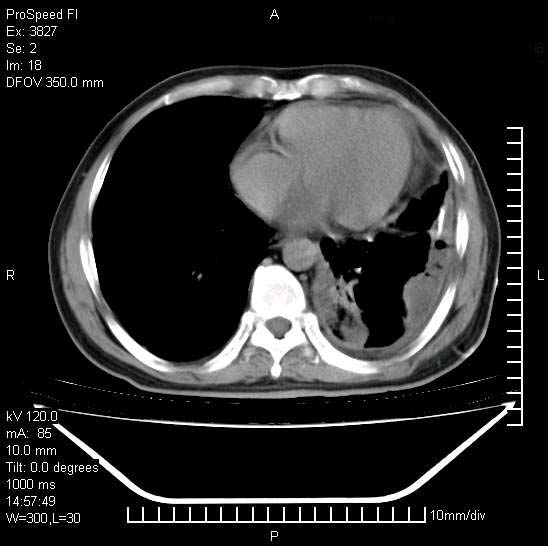

男性,一月前出现右侧肋区疼痛,较剧烈,干咳,无发热,自诉使用抗炎药后缓解,几天前又出现左侧剧烈疼痛,

发热,体温38。9,今天ct,考虑左侧包裹性脓胸,胸腔积液,右上中肺小斑片影,结核/炎症?胸水未见恶性细胞。